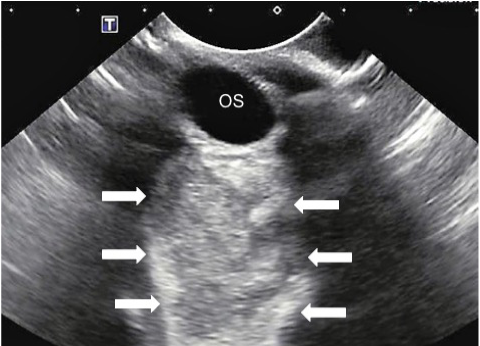

Figure 1

Ocular ultrasound of the left eye demonstrating a large hyperechoic retrobulbar space occupying lesion.